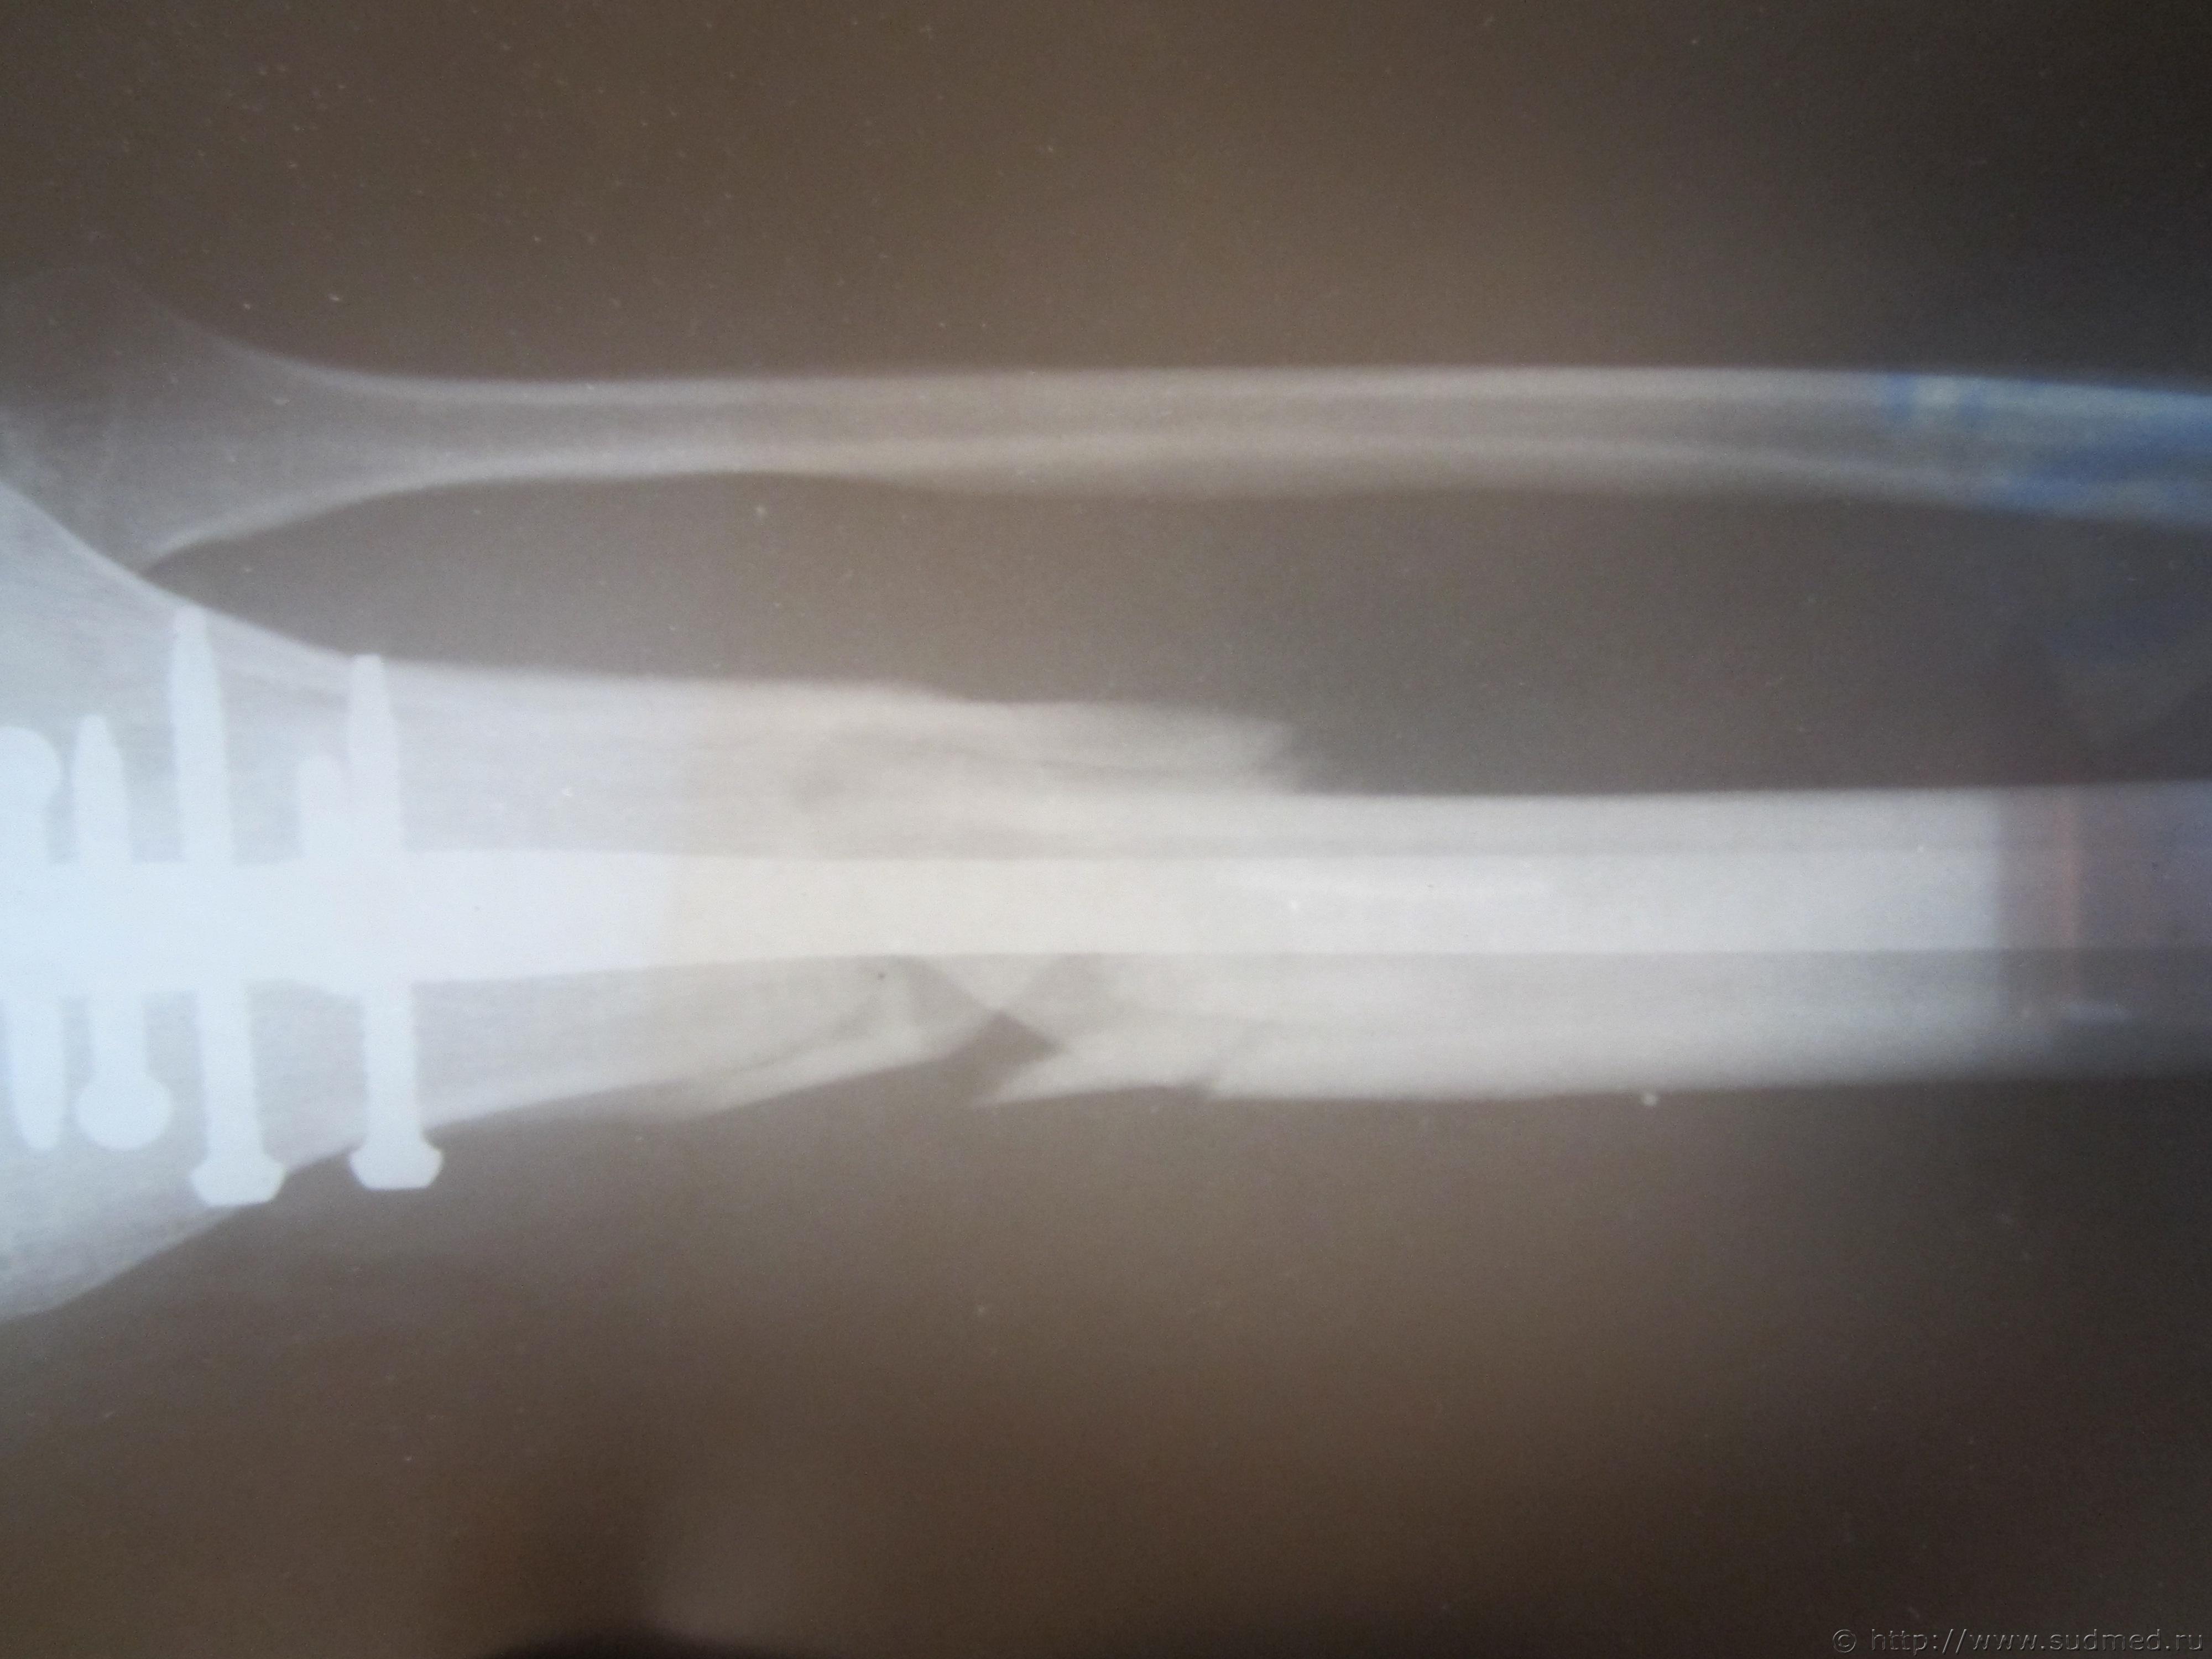

Выписка из истории болезни: Основной диагноз- закрытый оскольчатый перелом правой большеберцовой кости верхней трети со смещением осколков. Состояние на момент поступления- средней тяжести. Наложено скелетное вытяжение за пяточную кость. Лечение в стационаре- операция остиосинтеза правой большеберуовой кости блокированным штифтом.

Спасибо Вам заранее. Фоты прилагаю...

Судебная медицина - Прикрепленное изображение Судебная медицина - Прикрепленное изображение